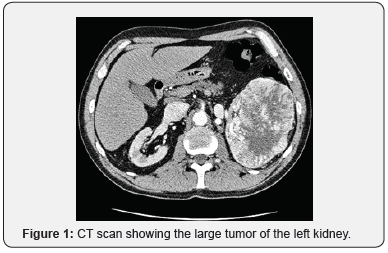

The uroscan by computed tomography showed a bilateral kidney tumor. The left one was very large measuring 12x8x9cm taking up the lower two-thirds of the kidney. There was also a lymphadenopathy and no left renal vein thrombosis. The right kidney was occupied by an heterogenous polar superior tumor, measuring 4.3x5.1x5cm. Screening for metastasis was normal.

The patient under went at first a left radical nephrectomy. The anatomopathological study revealed a clear cell renal cell carcinoma : Fuhrman grade 3, stage pT2N0. Two weeks later, a right partial nephrectomy was performed and histological analysis found a clear cell renal cell carcinoma : Fuhrman grade 2, stage pT1N0 (Figure 1).